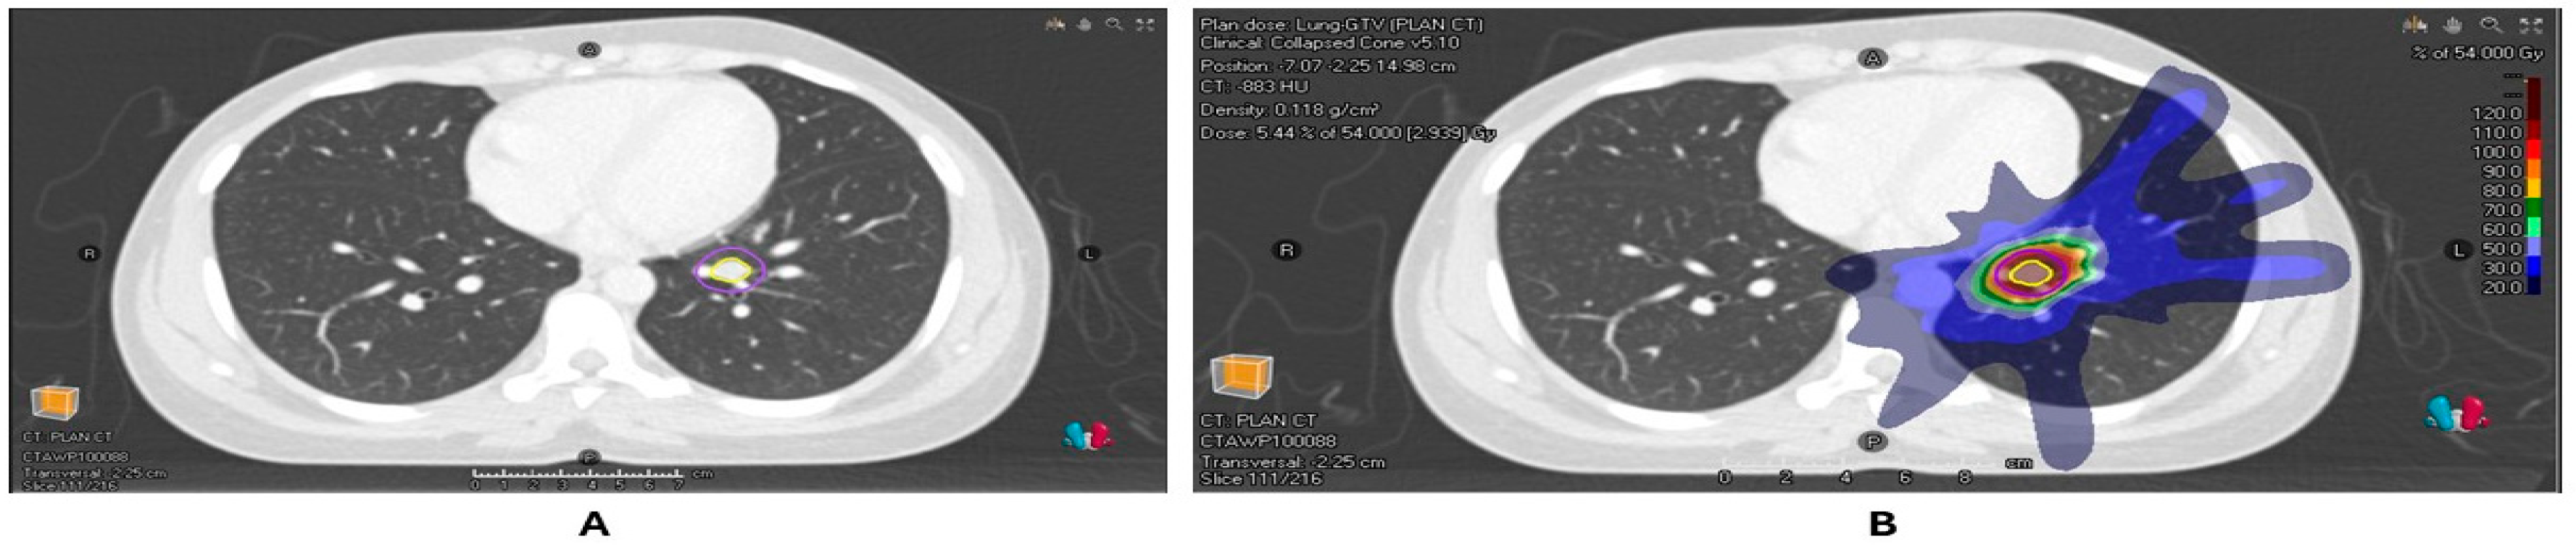

Figure 1.

(A) Radiotherapy planning scan of patient with a colorectal cancer metastasis in the left lower lobe of the lung with GTV and PTV contours. (B) Dose distribution of the planned SABR of 54 Gy/3#.